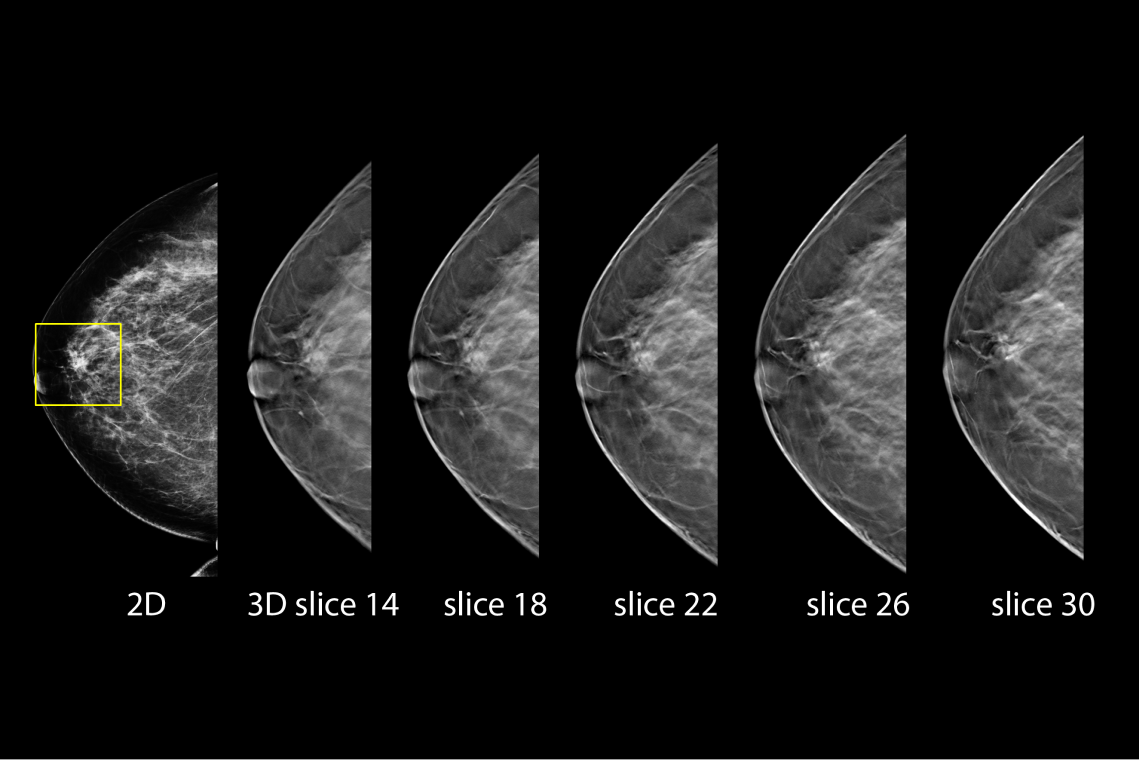

Hologic has further advanced breast cancer screening by producing 2D images from breast tomosynthesis data using C View software, resulting in a Low Dose Genius 3D Mammography exam with superior clinical performance compared with 2D alone.4

This Low Dose Genius 3D Mammography exam is performed in a rapid 3.7 second scan time for greater patient comfort and low patient dose, due to the elimination of 2D X ray exposures. The synthetic 2D images and 3D slices are reviewed together to make clinical decisions or diagnoses part of the Genius 3D Mammography screening exam.